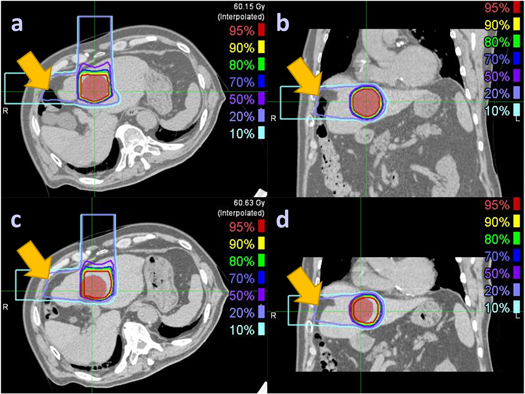

It is important to know the unsuitable conditions for the clinical use of the DVM method. The DVM CT is obtained by adjusting the VOI and BV of the PlanCT to match the DRRs of the adjusted PlanCT with the 2D setup images. Therefore, gastrointestinal tract motility in the beam paths during the treatment course cannot be estimated by the current DVM technique, as was the case with Patient 1 (figure 9). An unusual space was noticed between the abdominal wall and the liver. The large intestines could move into the space on the day of the CT simulation but be absent on the treatment day. The PTV coverage difference between InRoom-BM and DVM-BM for Patient 1 was high (−21.57%) but low (−3.09%) between InRoom-TM and DVM-TM. This substantial difference was mainly due to the PTV coverage difference between InRoom-BM (75.73%) and InRoom-TM (93.44%), resulting from liver deformation caused by the extrusion of the large intestines rather than DVM optimization errors, as the PTV coverage of the DVM-BM (97.3%) and DVM-TM (96.53%) were similar.

Figure 9. Liver deformation between PlanCT ((a) and (b)) and InRoom-BM ((c) and (d)) for Patient 1. The red-color wash regions denote the PTV, and the yellow arrows point out the unusual space that the large intestines could move into on the day of the CT simulation but be absent on the treatment day, making the liver deformed.

Download figure: